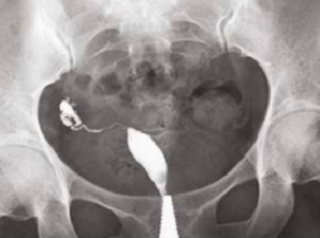

What does HSG assess?

-

Shape of the uterus

Normal shape

Unicornuate uterus

Complete septate uterus

Patency of fallopian tubes

Open tube

Closed tube

Uterine cavity

Clear/Normal

Submucosal fibroid

Adhesions/Synechiae